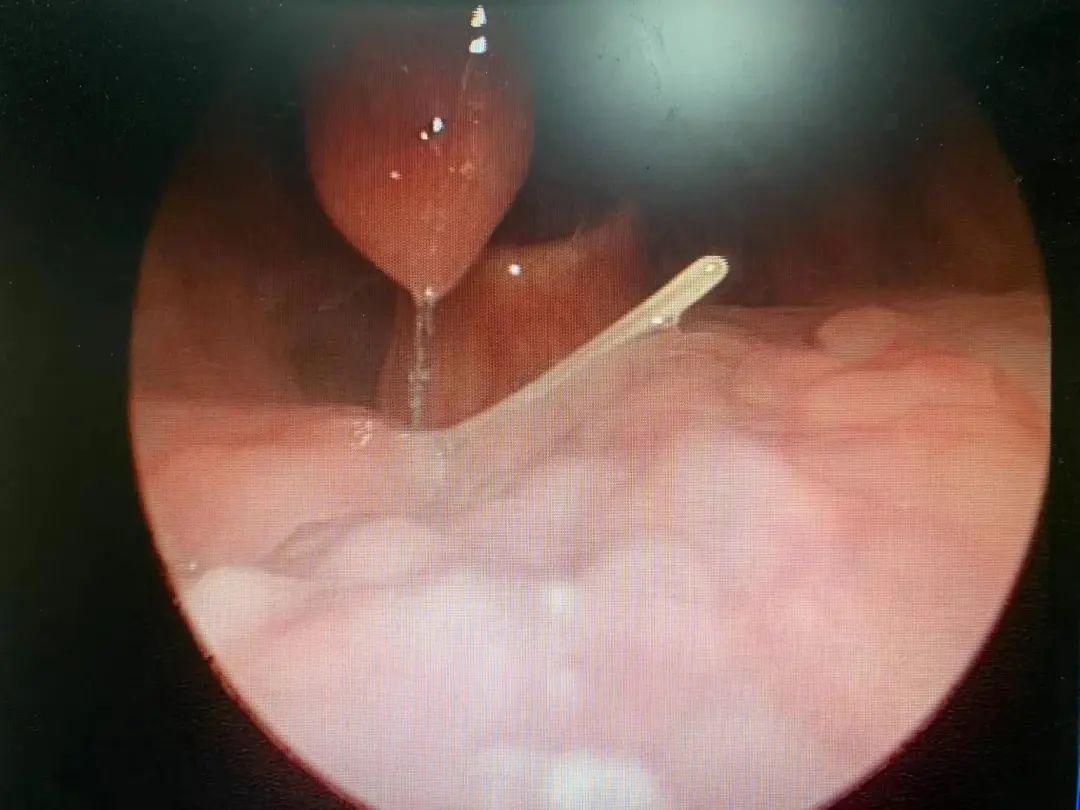

2月13日大年初四晚上,45岁的王女士(化名)看着下午刚买的鱼非常鲜活,特地在网上学了没有鱼刺的鱼汤的做法,家人们边喝鱼汤边聊天,都特别开心。为了不浪费,王女士喝掉了最后一碗鱼汤,但没想到就被鱼刺卡着了,喉咙处有明显的异物感。于是她来医院就诊,经检查,王女士的咽喉部扎着一根大约2厘米长的鱼刺,在喉镜下,医生将鱼刺取出。

喉镜下的鱼刺